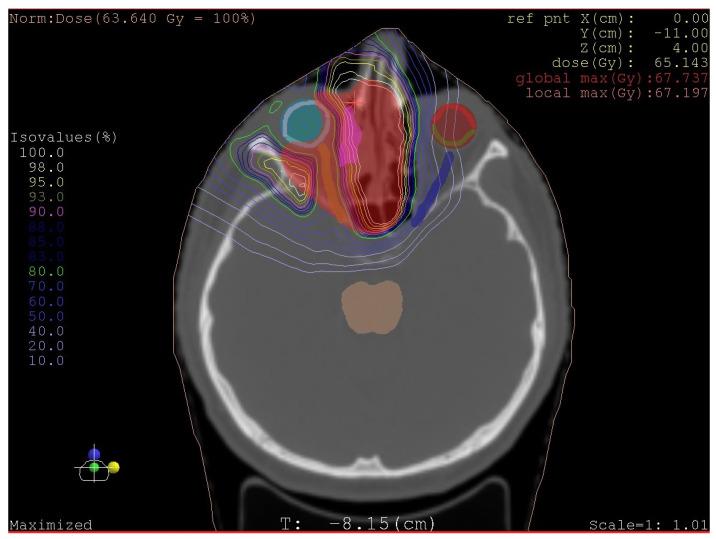

Sarcomas in the head and neck area are rare diseases with an incidence of under 1% of all head and neck malignant tumours. Osteosarcomas or osteogenic sarcomas consist of neoplastic cells that produce osteoid bone or immature bone. Sarcomas develop more in the mandible than the maxilla. The exact diagnosis of different types of sarcomas is based on the immunohistochemical investigation. These rare tumours are of mesenchymal origin; osteosarcomas and chondrosarcomas are the most common types-Ewing's sarcomas. The use of proton beam radiotherapy in the treatment of osteosarcoma of the maxilla is rarely reported in the literature. We present a case of successfully treated (surgery and proton beam radiotherapy) poorly differentiated highly aggressive osteosarcoma in the ethmoids and maxillary sinus and morbidity after the treatment. We were presented with a case of a 65-year-old man with anaesthesia and palsy of the right face. The stomatology department performed the extraction of a tooth. One month later, the wound was still open. The histology showed an osteogenic sarcoma in the area of the wound. The oncologist and maxillofacial surgeons in a catchment hospital recommended a nonsurgical approach. Hence, we performed a radical maxillectomy and ethmoidectomy, after which we continued with proton bean radiotherapy. The patient is now five years after therapy without signs of sarcoma; however, he has blindness in the right eye and reduced vision in the left eye, as well as gliosis of the brain, vertigo, tinnitus, trismus, and ancylostomiases. Head and neck osteosarcomas treatment is considered a complex multidisciplinary task. It is currently argued that there is no clear therapeutic protocol for successful treatment. Innovations in treatment modalities such as proton beam radiotherapy appear to have potential, although their effects on long-term morbidity and survival outcomes are still undetermined. We present a rare case report of an osteosarcoma of the maxilla involving an innovative, successful treatment procedure combining surgical excision followed by proton beam radiotherapy. This treatment approach may enable maximum tumour control. This protocol has not been adequately described in the world literature for this diagnosis.

头颈部肉瘤是一种罕见疾病,发病率低于所有头颈部恶性肿瘤的 1%。骨肉瘤或成骨肉瘤由产生骨样骨或未成熟骨的肿瘤细胞组成。肉瘤在下颌骨比上颌骨更常见。不同类型肉瘤的准确诊断基于免疫组织化学研究。这些罕见的肿瘤来源于间充质;骨肉瘤和软骨肉瘤是最常见的类型——尤因肉瘤。质子束放疗在治疗上颌骨骨肉瘤中的应用在文献中很少报道。我们报告了一例成功治疗(手术和质子束放疗)的筛窦和上颌窦未分化高度侵袭性骨肉瘤病例,以及治疗后的发病率。我们报告了一例 65 岁男性,出现右侧面部麻醉和瘫痪。口腔科进行了拔牙。一个月后,伤口仍未愈合。组织学显示伤口处有骨肉瘤。收治医院的肿瘤学家和颌面外科医生建议采用非手术方法。因此,我们进行了根治性上颌骨切除术和筛窦切除术,之后继续进行质子束放疗。患者在治疗后五年无肉瘤迹象,但右眼失明,左眼视力下降,同时伴有脑胶质增生、眩晕、耳鸣、牙关紧闭和Ancylostomiases。头颈部骨肉瘤的治疗被认为是一项复杂的多学科任务。目前认为,对于成功治疗,尚无明确的治疗方案。治疗方式的创新,如质子束放疗,似乎具有潜力,尽管其对长期发病率和生存结果的影响仍不确定。我们报告了一例罕见的上颌骨肉瘤病例,采用了一种创新的、成功的治疗方法,结合了手术切除和质子束放疗。这种治疗方法可能能够最大限度地控制肿瘤。这种方案在世界范围内针对这一诊断的文献中尚未得到充分描述。